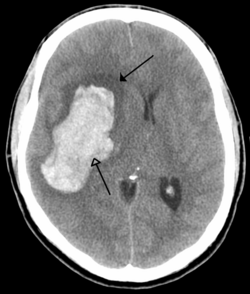

CT scan of an intraparenchymal bleed (bottom arrow) with surrounding edema (top arrow)

There are two main types of hemorrhagic stroke:[29][30]

• Intracerebral hemorrhage, which is bleeding within the brain itself (when an artery in the brain bursts, flooding the surrounding tissue with blood), due to either intraparenchymal hemorrhage (bleeding within the brain tissue) or intraventricular hemorrhage (bleeding within the brain's ventricular system).

• Subarachnoid hemorrhage, which is bleeding that occurs outside of the brain tissue but still within the skull, and precisely between the arachnoid mater and pia mater (the delicate innermost layer of the three layers of the meninges that surround the brain).